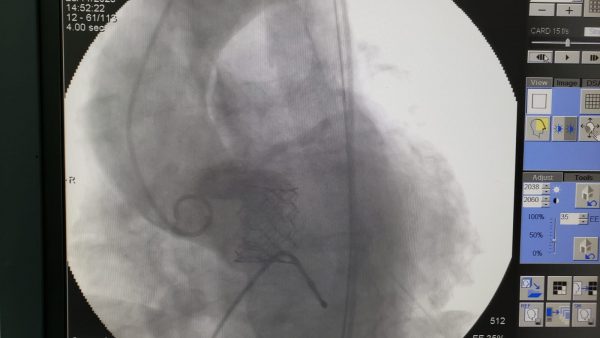

O Hospital Metropolitano Vale do Aço, unidade de referência a beneficiários da Unimed Vale do Aço, registrou a realização de um procedimento inédito em sua hemodinâmica: o primeiro implante percutâneo de válvula aórtica (TAVI) com prótese balão expansível. O procedimento, que é minimamente invasivo, ou seja, sem a necessidade de cortes, como nas cirurgias abertas, ocorreu nesta terça-feira. A paciente se recupera bem.

Além disso, segundo o médico, se trata de um procedimento novo, que traz mais segurança ao paciente em tratamento de estenose aórtica grave. “A principal diferença é que se trata de um procedimento sem incisões cirúrgicas (sem necessidade de abrir o peito). Na cirurgia convencional o tórax fica aberto e é feita a parada cardíaca, em que o sangue circula por uma máquina – circulação extracorporea. Neste procedimento, a válvula é implantada por cateter através de uma punção e posicionada com a ajuda do raio-X”, esclareceu.